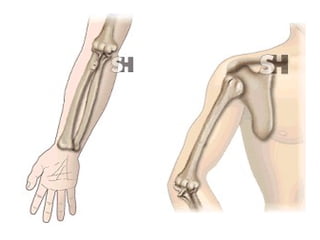

HOMBRO BRAZO CODO ANTEBRAZO MUÑECA MANO Monteggia Colles Fx escafoides

HOMBRO BRAZO CODOANTEBRAZO MUÑECA MANO Monteggia Colles Fx escafoides